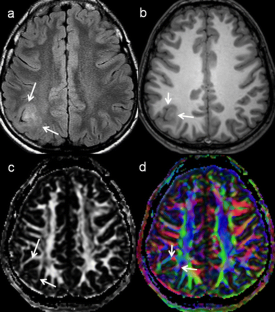

Fig. 4